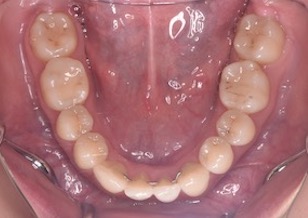

矯正後

After Ⅱ

マルチブラケット装置を装着し、左側上下顎第1大臼歯部にクロスエラスティックス(患者さん自身で付け外しのできる輪ゴム)を装着していただき大臼歯部の交叉咬合の改善を行いました。上顎左右第1小臼歯2本と下顎の左側側切歯の合計3本を便宜抜歯して歯列の整直と咬合の確立を行いました。また治療上の工夫としてIPR(エナメルストリッピング)を数カ所において行いました。

その結果、上下顎の歯並びは整直されともにキレイな歯並びとなりました。左側第1大臼歯部の交叉咬合ならびに側切歯部の反対咬合は改善され、全てのエリアで正常な咬み合わせになりました。